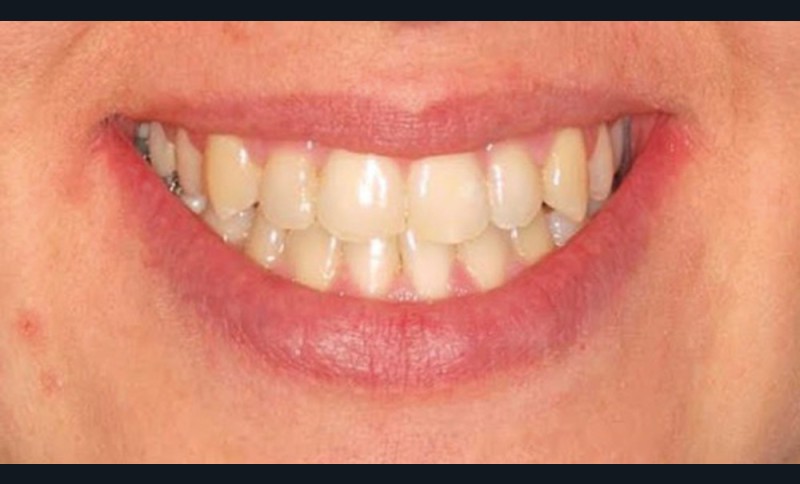

Le Pr Olivier Sorel insistera sur l’importance du respect des formes et des proportions anatomiques, pour éviter de voir apparaître, notamment chez les adultes, de très inesthétiques triangles noirs lors de la phase d’alignement (fig. 6a-b). Il présentera sa démarche diagnostique (évaluation de la forme des dents et de la dysharmonie dento-dentaire, fig. 7a-c) et l’intégration de la réduction amélaire proximale au plan de traitement, afin de s’assurer, en fin de traitement, la présence de papilles gingivales et donc d’un sourire harmonieux (fig. 8a-d).

Les Drs Marie Clément et Clara Marcoux aborderont ensuite les différents apports de la dentisterie esthétique aux traitements orthodontiques. Les problèmes de dyschromies isolées ou généralisées, congénitales ou acquises seront développés ainsi que les anomalies de proportions dentaires (dents riziformes…), le maquillage (transformation d’une canine en incisive latérale…) et le remplacement des dents antérieures. Les auteurs présenteront l’intérêt du Digital Smile Design dans le diagnostic et la communication et l’arsenal thérapeutique à notre disposition pour améliorer la satisfaction de nos patients (éclaircissement, traitement des taches de l’émail, composites stratifiés, fig. 9a-d).